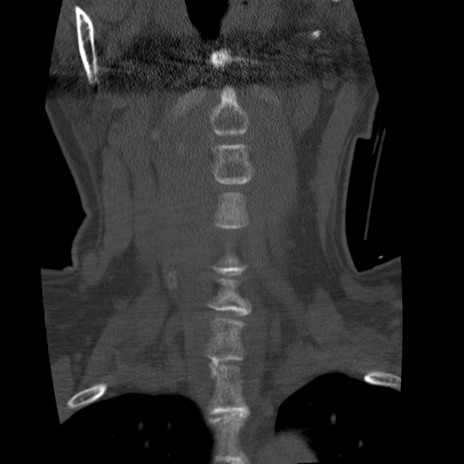

症例50 頚椎CT(冠状断像)

異常所見と診断は?

頚椎CT